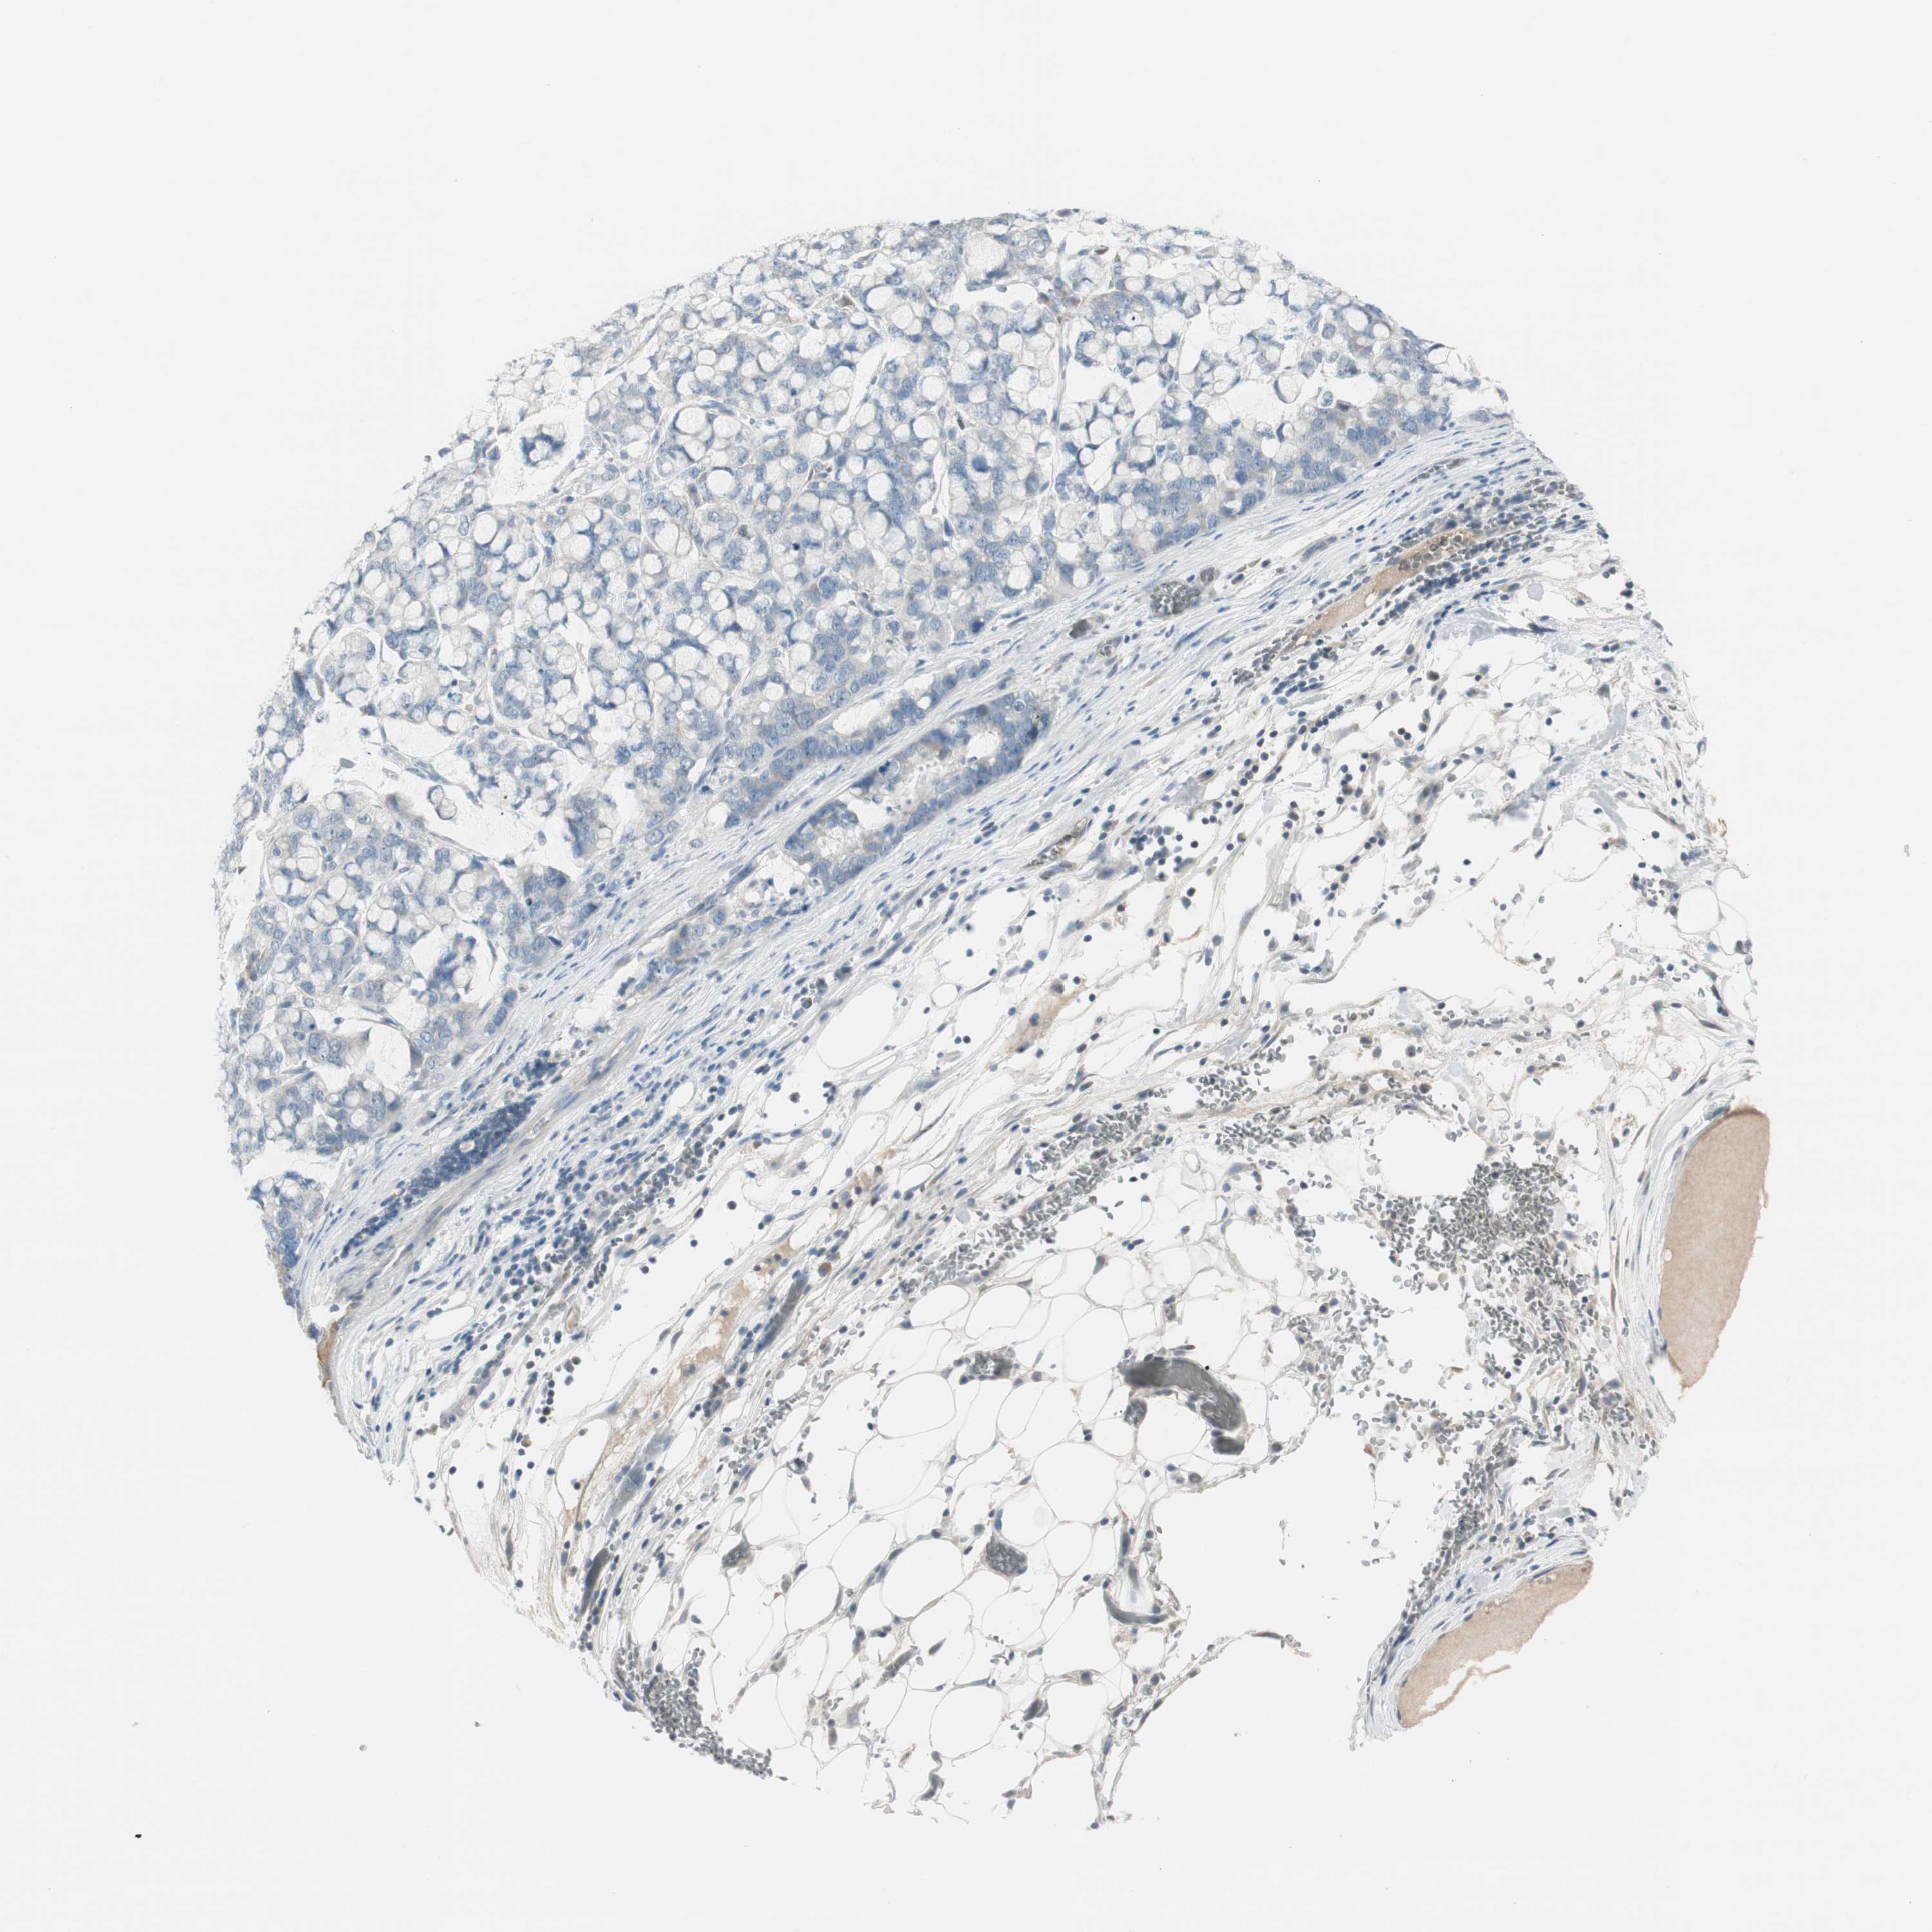

STOMACH CANCER - Protein expressioni

A mouse-over function shows sample information and annotation data. Click on an image to view it in a full screen mode. Samples can be filtered based on level of antibody staining by selecting one or several of the following categories: high, medium, low and not detected. The assay and annotation is described here.

Note that samples used for immunohistochemistry by the Human Protein Atlas do not correspond to samples in the TCGA dataset.

Antibody stainingi

Antibody staining in the annotated cell types in the current human tissue is reported as not detected, low, medium, or high, based on conventional immunohistochemistry profiling in selected tissues. This score is based on the combination of the staining intensity and fraction of stained cells.

Each image is clickable and will lead to virtual microscopy that enables deeper exploration of all samples and also displays staining intensity scores, fraction scores and subcellular localization as well as patient and tissue information for each sample.

Antibody HPA008055

Staining

High

Medium

Low

Not detected

Intensity

Strong

Moderate

Weak

Negative

Quantity

>75%

75%-25%

<25%

None

Location

Nuclear

Cytoplasmic/membranous

Cytoplasmic/membranous,nuclear

Adenocarcinoma, NOS

Adenocarcinoma, High grade